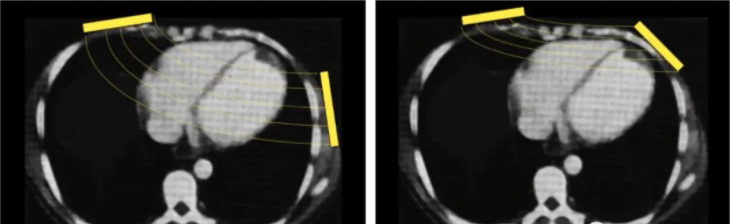

在2003年在《复苏》期刊发表的研究有相关内容的解释(如下图所示)

内容提到一个重要专业名称——经胸阻抗(Transthoracic impedance, TTITTI是决定体外除颤过程中跨越心肌电流幅度的重要因素,最小化TTI增加了除颤的成功机会。

大多数AED电极片的形状为矩形,因此可以横向或纵向放置,尤其是心尖位的电极片。

从理论层面上,横向放置的电极片边缘接触较差,可能会导致TTI高于纵向放置。

研究得出结论为: 矩形除颤板的纵置方向产生的TTI比水平方向较低 。